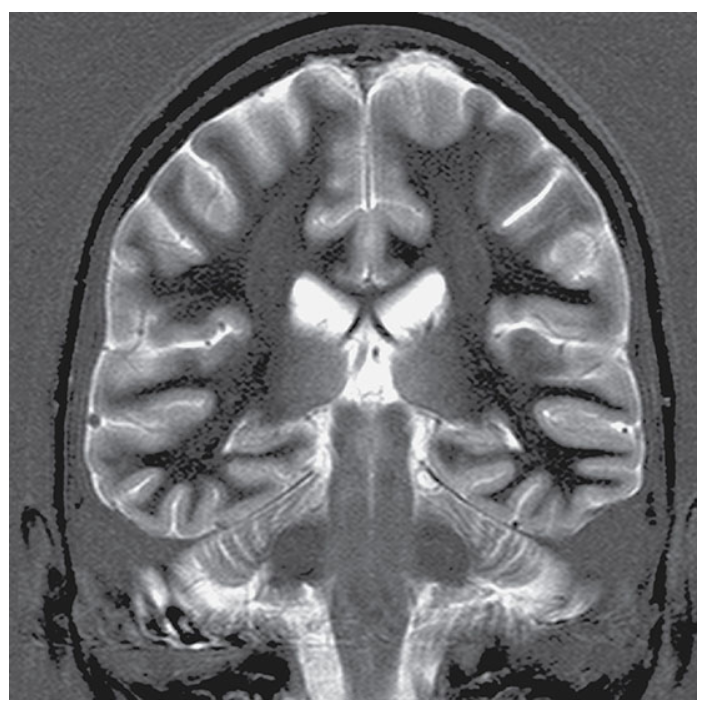

Coronal IR-TSE T2-weighted image with a TI selected to null white matter.